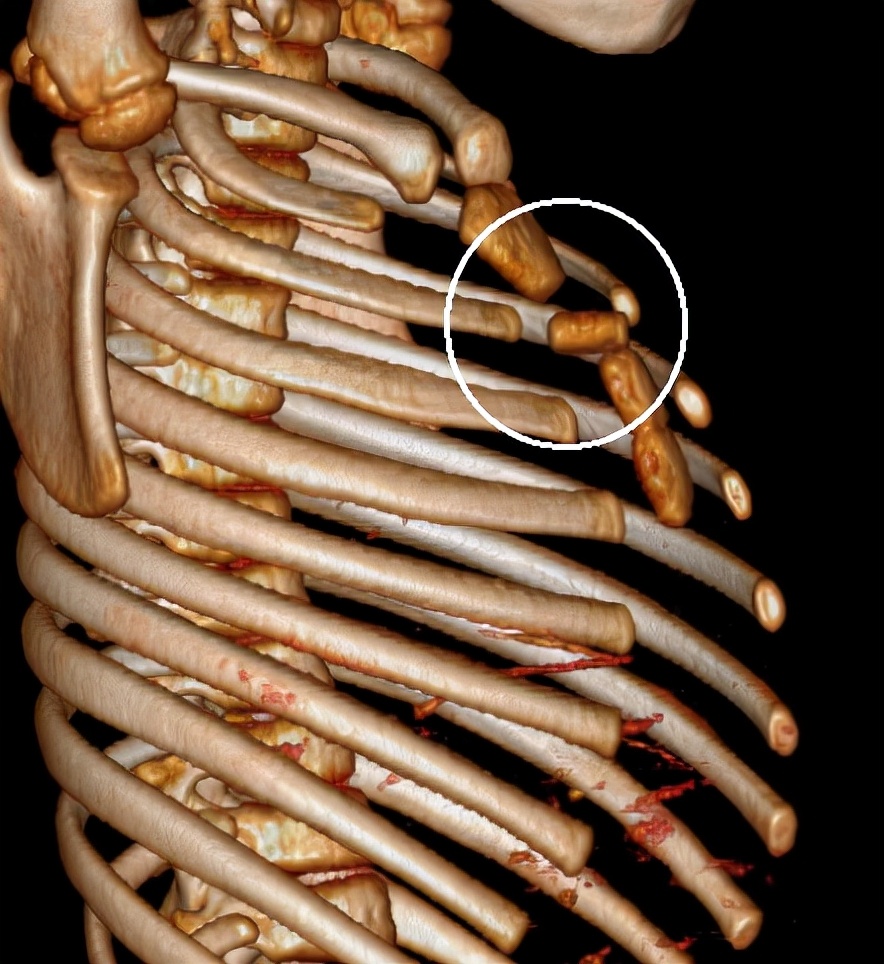

入院查体:前胸壁正中隆起,具有有明显压痛,胸骨局部活动。X线检查提示胸骨角与胸骨体之间骨折。局部骨骼与胸骨体成角。胸壁骨骼三维重建提示胸骨局部离断,离断部位为胸骨体上段。术前诊断为继发性胸廓畸形,胸骨粉碎性骨折。经充分术前准备,今日上午实施手术治疗。术中采用正中切口,游离胸骨。术中见胸骨角下方胸骨离断,离断长度约1CM,与胸骨体完全分离,局部无明显活性。将离断胸骨部分清除,以MatrixRIB重建胸骨。术野留置引流管,关闭切口,手术结束。

(三维重建显示胸骨离断)